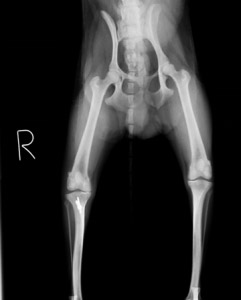

術後レントゲン:

膝蓋骨が正常な位置に整復されました。術後は2日目から歩行可能になり、術後2週目にはほぼ正常に歩けるようになりました。

再脱臼などの合併症もなく経過良好でした。